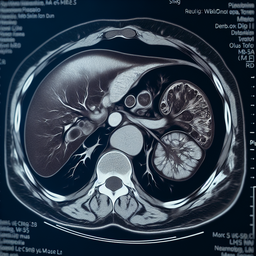

МРТ селезінки

МРТ (магнітно-резонансна томографія) селезінки — це неінвазивний метод дослідження, який дозволяє отримати детальне зображення цього органу. Він використовується для виявлення різних патологій, таких як пухлини, абсцеси, травми або інші структурні аномалії.